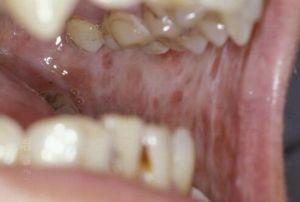

本病好發於20~40歲者,男女性別差異不大,易發於頰、軟齶、唇、舌、口底、咽等部位。早期無症狀,以後口腔有燒灼感,尤其在進食刺激性食物時更為明顯。大多早期出現皰,破潰後形成潰瘍。有的有自發痛、口乾、味覺減退。後期開口困難,不能吹口哨及吹滅蠟燭,張口受限,言語及吞咽困難。口腔黏膜變白,輕度不透明,觸診發硬,可發現纖維條索。舌病變時舌乳頭萎縮,運動受限(圖1~13)。